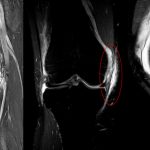

Fissurazione del Menisco: Cos’è , Cause, Terapie e Intervento